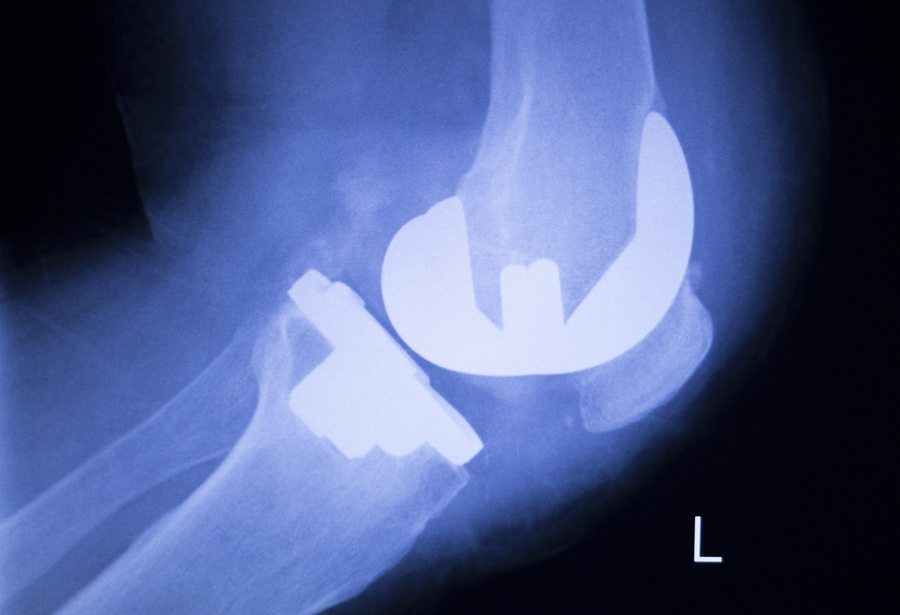

The Zimmer Knee is an artificial knee made of plastic and metal components. It replaces damaged or degenerated knee cartilage caused by osteoarthritis, rheumatoid arthritis and knee trauma. Some people who had a knee replacement with these products had to have a follow-up surgery when the replacement knee loosened prematurely, which has led to Zimmer Knee lawsuits

Doctors use metal components to cap the ends of the femur and tibia. These caps are usually attached with surgical cement. A plastic component replaces the damaged cartilage. The new knee joint creates a pain-free surface that glides easier.